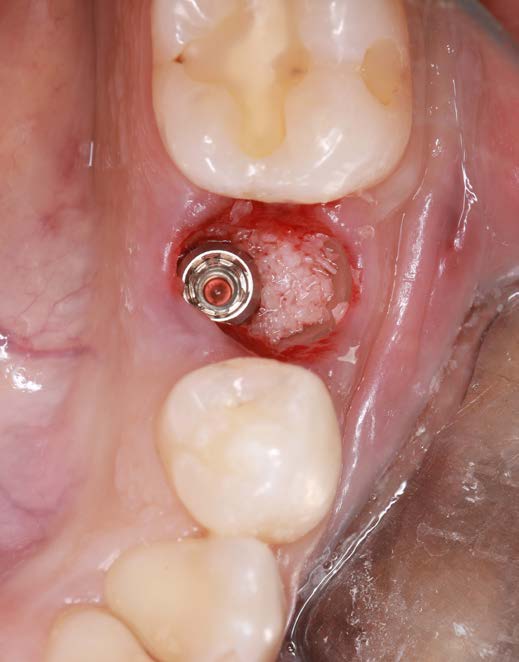

Figure 5: Condition after bone augmentation.

The Socket Shield Technique is not easy to perform. High-quality instruments are essential. Cuts must be fine and precise with minimal pressure. For this case, I used the H254LE 314 012 bone mill (Komet Dental) with a cross-cut design (right-right fluting), which runs smoothly and cuts efficiently. Its thin cut and controlled use in a red contra-angle handpiece make it ideal. I used it to section the tooth and shape the root remnant. Then, I refined the root with instruments 8831L, 831LEF, and ZR8801L (Komet Dental) - all of which allow fingertip control and effective cutting.

After osteotomy, I placed a 3.75 mm diameter implant, filled the gap between implant and root surface with allogenic bone substitute, inserted a provisional, and later restored with an aesthetic ceramic crown.